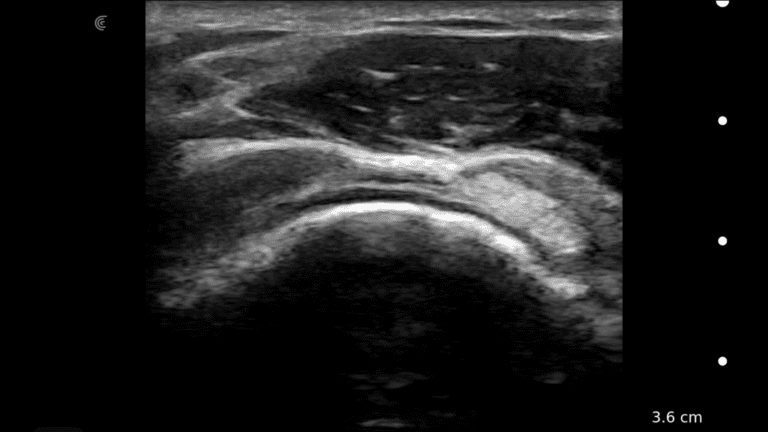

A survey scan of the elbow can identify some of the most common pathologies that cause acute and chronic elbow pain such as tendinosis of the common flexor or extensor tendons, joint effusion, or olecranon bursitis.